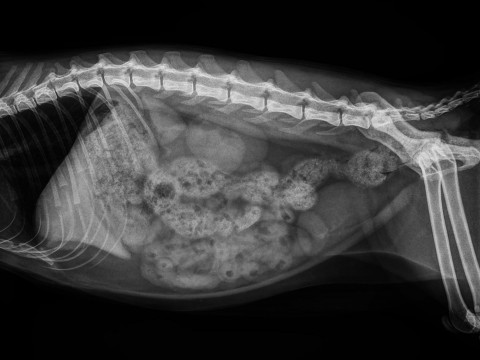

X光